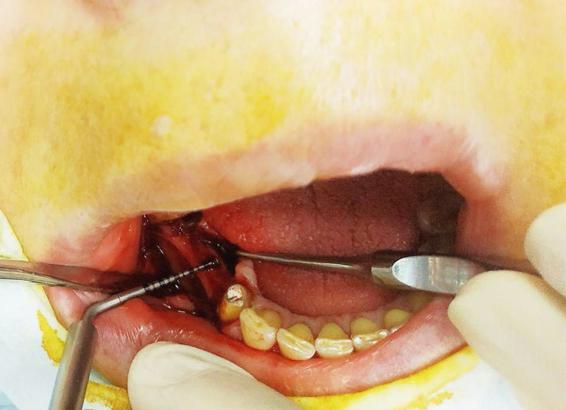

Лечение: Принято решение о пересадки ее собственной кости из угла челюсти. Отслоение слизисто-надкостничного лоскута. Забор блока кости в области угла челюсти. Остеопластика блоками + ксенографт. Установка двух имплантов. Наложение швов.